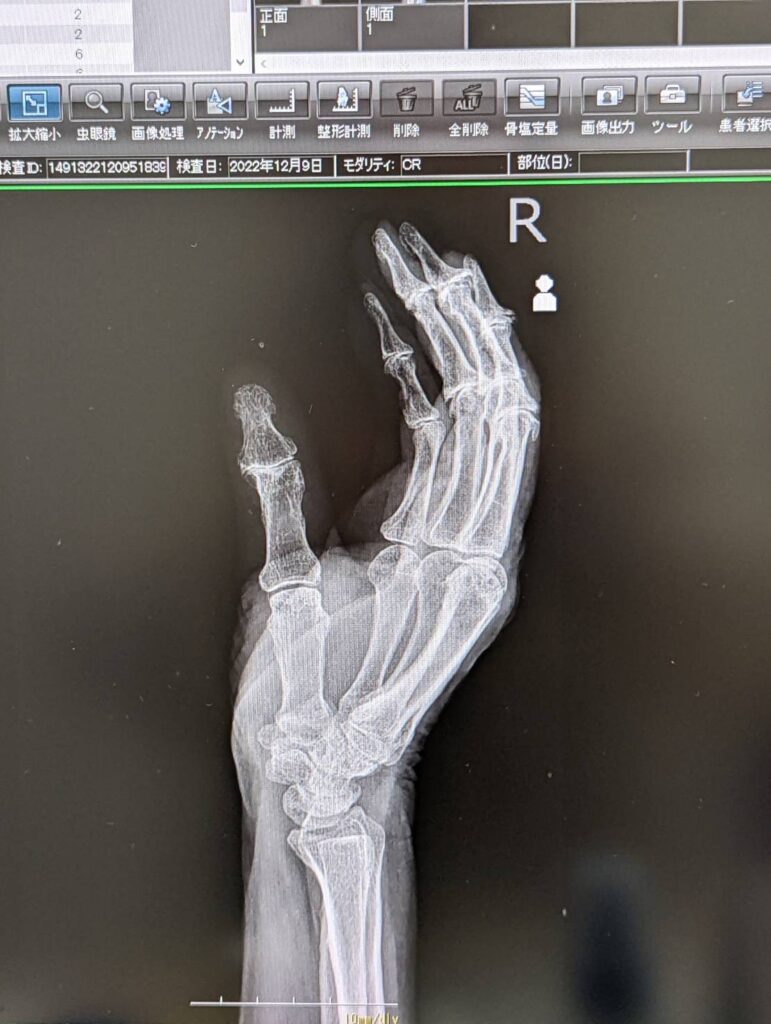

私の祖母の場合は、昨年12月中頃に右手の親指の動きが悪くなり、痛みも出ていたので整形外科を受診したところ、骨に問題はなく「ばね指」と診断されました。